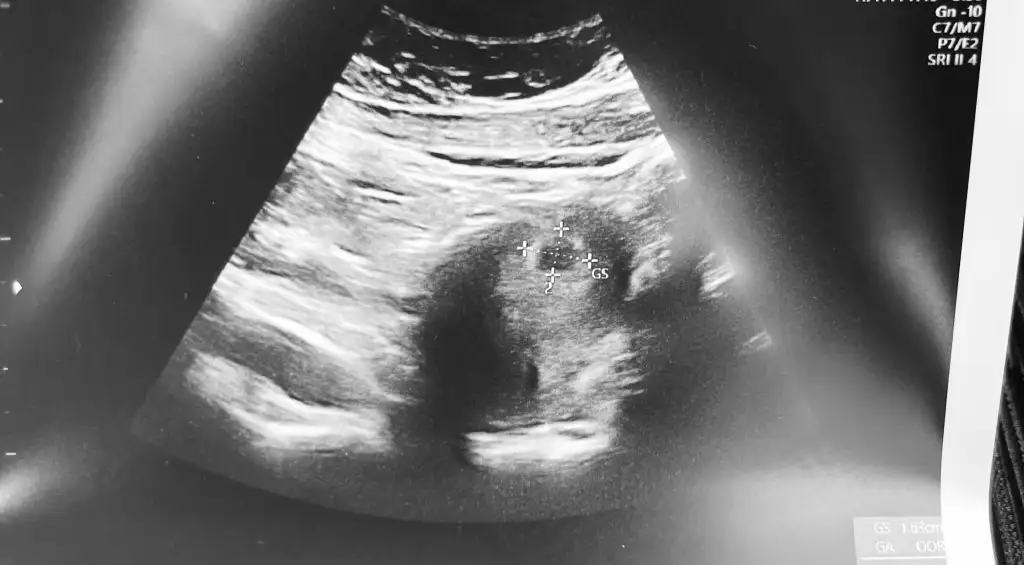

Merhaba bebegi gorup kalp atisini diymaniza cok sevindim. Adetiniz kac gun gectikten sonra gordunuz bebeginizi. Benim adet gunumun gecmesinin 13.gunu 6 haftalik gorunuyor kesem 12mm olmus yolk var ama icinde bebek yok.. yardim eder misiniz sizinde oyle miydi? Saglikla bebginizi kucaginiza almanizi diliyorum. 💜

Bende ayni durumdayim 6 haftalik kese 12mm yolkta var ama bebek yok :KK43: insallah 10 gune olusur.mucizem benle kalir:KK43: seninde oyle insallah💜💜